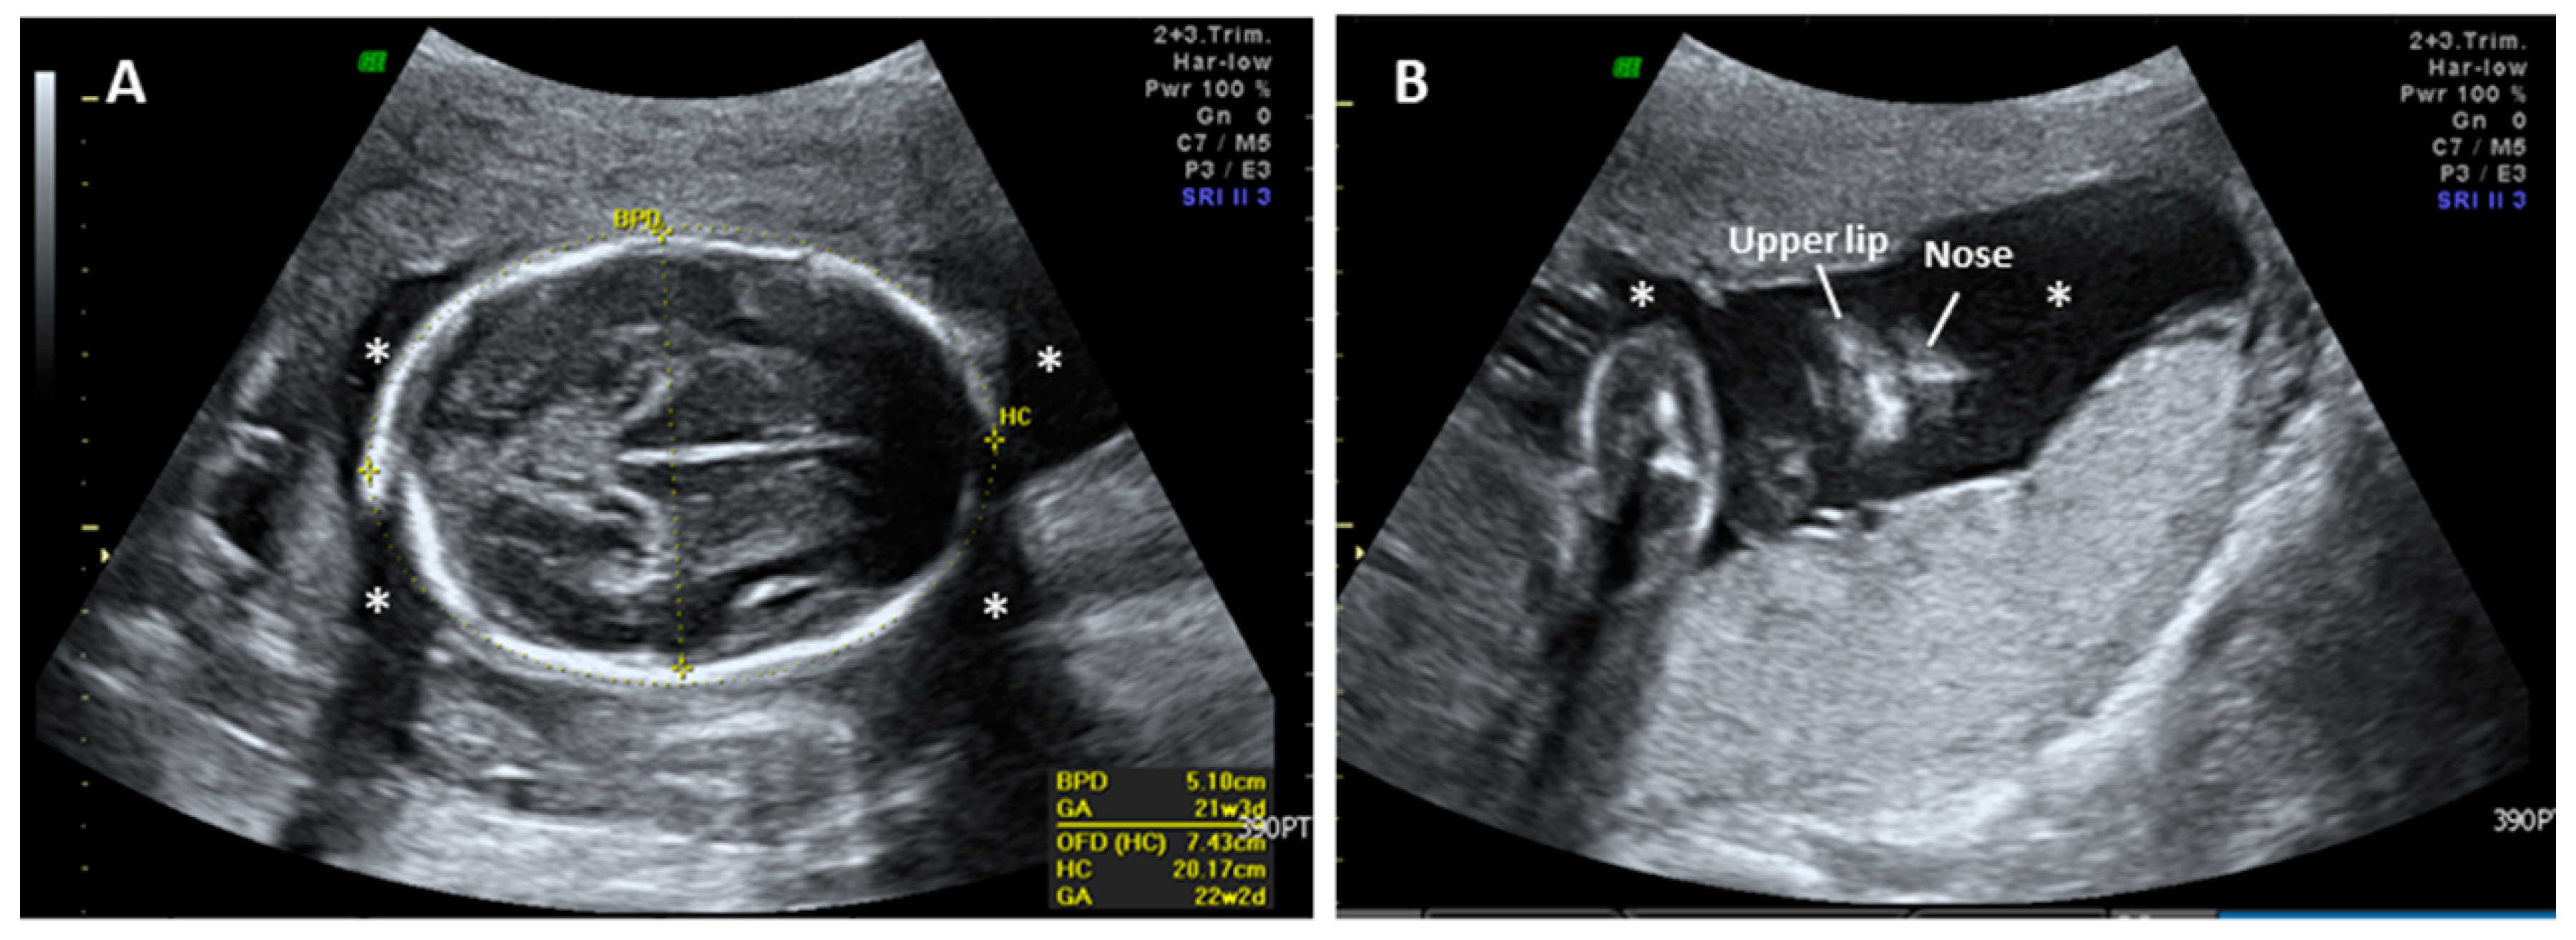

2. Case Report